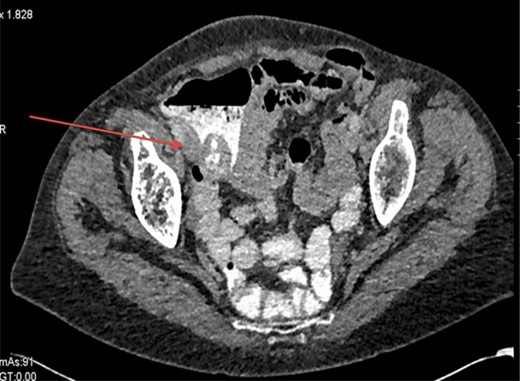

Shown in Fig. 2 is a CT scan showing the caecal mass near to the ileocaecal valve.